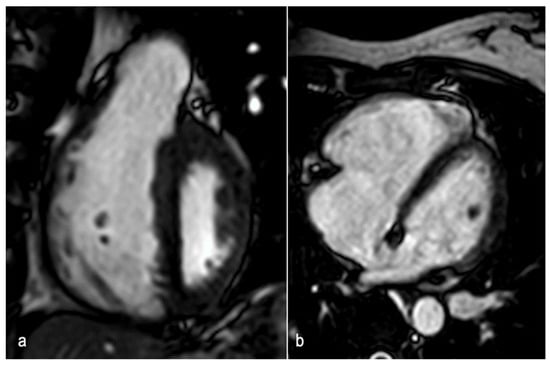

Emerging evidence suggests the potential diagnostic and prognostic value of CMR in managing patients with SCAD. CMR should be considered to confirm myocardial infarction when the diagnosis is uncertain, to assess the extent of myocardial involvement, and to investigate other possible etiologies and complications [92]. In a case-control study involving 158 SCAD survivors with angiographically confirmed diagnoses, Al-Hussaini and colleagues found that most patients with SCAD had no or small infarctions, with a preserved ejection fraction on follow-up CMR. However, those presenting with STEMI, reduced flow on ICA, multivessel SCAD, or signs of connective tissue disorders were more likely to have larger infarctions [93]. CMR abnormalities in SCAD patients may resemble those observed in patients with myocardial infarction from other causes. A standard CMR protocol should include sequences that provide an adequate morpho-functional and tissue characterization [94]. Cine-MRI sequences (two-dimensional SSFP technique) enable the assessment of wall thickness, ventricular volumes, ejection fraction (EF), and wall motion abnormalities in the affected coronary territory [90]. The presence of myocardial edema can be detected in T2-weighted short tau inversion recovery (STIR T2w) images as wall hyperintensity. Perfusion defects in resting perfusion study and microvascular obstruction in early gadolinium enhancement (EGE) imaging may be identified. The evaluation of myocardial viability is conducted using delayed-enhancement sequences, which can reveal areas of late gadolinium enhancement (LGE) with subendocardial or transmural patterns in the involved coronary territory (Figure 6) [95].

Figure 6.

A 36-year-old woman at week 36 of pregnancy presented with chest pain and anterior ST-segment elevation on ECG. CMR detected edema in the LAD territory in STIR sequence (a), confirmed by increased T2 mapping values in the same territory, with maximum values in the mid-ventricular anterior and anteroseptal segments (b,d), consistent with recent infarction-related changes. LGE with ischemic subendocardial pattern in LAD territory is depicted in delayed-enhancement sequence (c). CMR: cardiac magnetic resonance; LAD: left anterior descending artery; STIR: short tau inversion recovery; and LGE: late gadolinium enhancement.

Finally, the implementation of quantitative T1- and T2-mapping techniques has significantly enhanced the accuracy of detecting myocardial edema and scar tissue, providing valuable insights into the extent of cardiac damage and aiding in the assessment of myocardial viability.